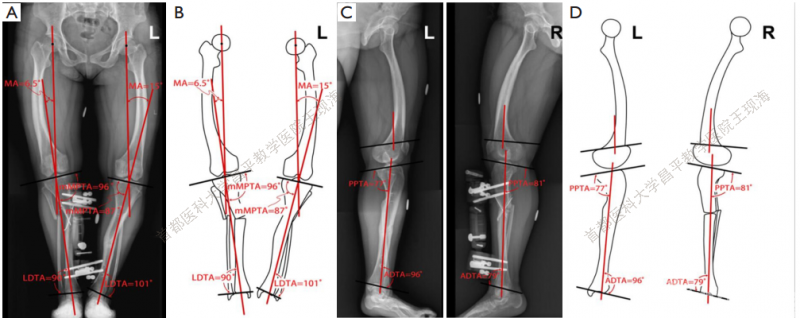

下肢外观有所改善。CORA的平均位置如下:左侧在膝关节方向线上17厘米,右侧在膝关节方向线上12 cm。畸形的评估修正,MPTA改善,左侧由76°-到87°,右边由72°到 96°(Figure 4A,B and Table 2) 。mLDTA,左边从109°到 101°,右边从98°到90°(Figure 4A,B and Table 2) 。

图4在冠状面和矢状面测量的术后关节方向角。(A)冠状面X线;(B)冠状面下肢轮廓;(C)矢状面X线;(D)矢状面下肢轮廓。

矫正后的双侧力线较术前均明显改善(表 2) 。在最后一次就诊时,PPTA和ADTA接近正常值,得到了明显的矫正(图 4C,D, 表 2) 。在上次访问中,双侧骨质均已愈合(图 5) 。

对于实际的单水平截骨根据术后影像进行假体的调整(图6)。对于多水平截骨的在采用模拟图像后选择相应的假体。股骨远端和胫骨近端截骨量与相应的假定机械轴平行(表 3) 。选择适当大小的股骨和胫骨侧的部分,使其覆盖没有超出皮质。

图6 二维TKA术前计划。(A)在术后X线上使用相应的模板对每侧进行大小调整;(B)在多水平截骨术后的模拟图像中,使用相应的模板对每一侧进行尺寸大小的测量。

单水平截骨的双侧均行3Dtka术前计划。三维重建后,胫骨平台有3°后角(图7) 。所使用的种植体尺寸和3D解剖模型都被描述。

图7 单水平截骨术后三维模拟TKA术前计划。(A)下肢的冠状面重建;(B)右下肢的矢状面重建;(C)右下肢的矢状面重建;(D)左侧胫骨平台,从尖端到截骨面为11毫米;(E)右侧胫骨平台,从尖端到截骨面为14毫米;(F)左胫骨切面;胫骨组件使用3号;(G)右胫骨切面,胫骨组件使用2号。

三维分析显示,在右侧胫骨平台内侧最高点到截骨面的距离为14毫米,已进行了校正。左侧为11mm。由于胫骨解剖轴与机械轴成角,在右侧有可能发生胫骨假体柄与胫骨外侧皮质的撞击。